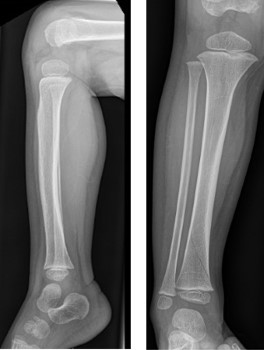

- X-rays are taken which show a broken bone near the ankle (see pictures below).

- If the X-ray doesn’t show a broken bone, it might still be broken. This is called a “suspected toddler’s fracture.”